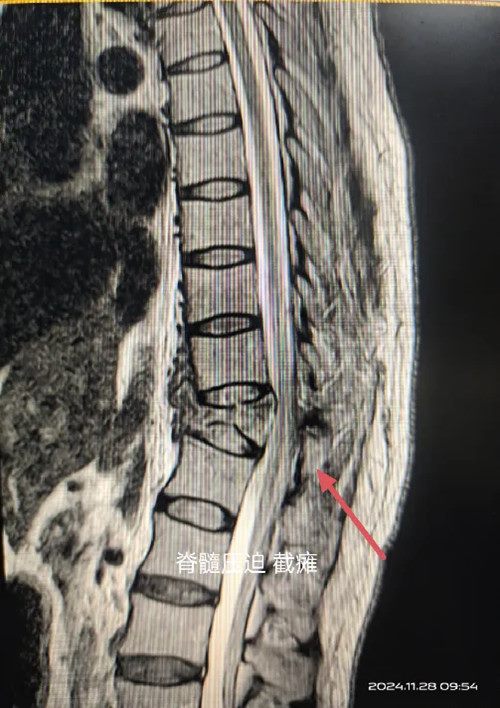

查体见患者双下肢无明显肌肉活动迹象

仅残存部分皮肤感觉

诊断为胸椎爆裂骨折并截瘫

FrankelB级属严重脊髓损伤

核磁显示骨折块压迫,局部脊髓变细

如不尽快解除压迫将造成不可逆性损伤

瘫痪等严重后果